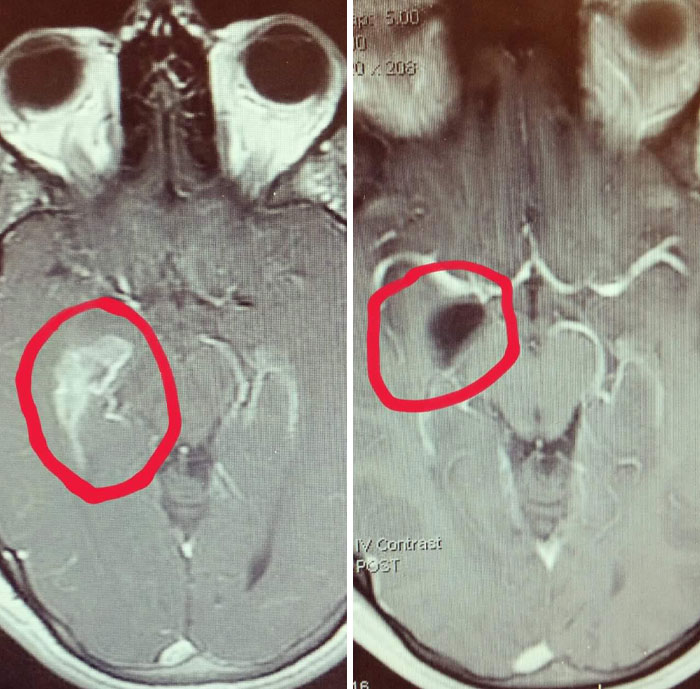

#3 Môj mozog pred a po operácii